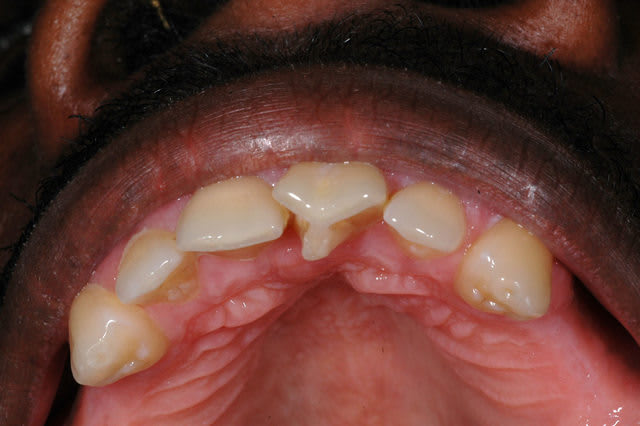

... ma gamine, bientôt 9 ans.

Père CD ... traitement d'ortho.

Mère CD ... traitement d'ortho.

Les conseils sont les bienvenus.

... je vous rassure, le reste de la gamine est lui plutôt réussit.

... pas de rapport avec Tchernobyl ... enfin j'espère!

1 0606 qvqx10 - Eugenol

2 0606 cmnadc - Eugenol

3 0606 btwdg4 - Eugenol